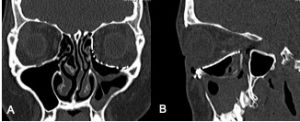

Postoperative imaging of orbital implants

Imaging of orbital fractures is indicated postoperatively to ensure accurate placement of orbital implants, occasionally when postoperative complications arise and when revision surgery is planned. This not only helps identify positioning of implants, but also assess orbital volume and soft tissue consequences and also guide additional surgery when indicated. While metallic implants are radioopaque and easily visible (figure 13 and 14) and easily visualized on bone and soft tissue windows, porous polyethylene implants and bioresorbable implants are more radiolucent and better visualized in soft tissue windows (Figure 15). Examples of suboptimal and good reconstruction with implant characteristics are shown below (Figure 16 and 17).